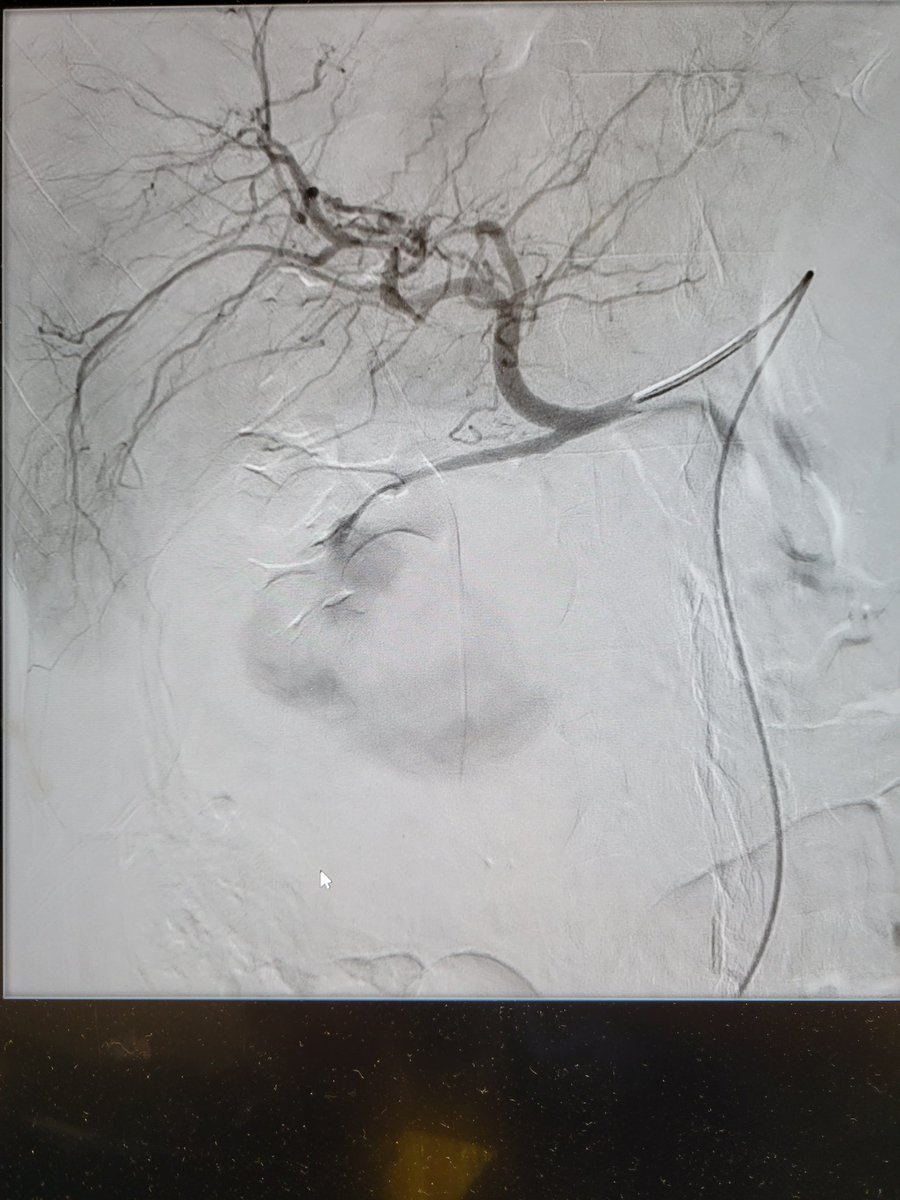

Great case and amazing job #irad #interventionalradiology

Patient presents with abdominal pain and distention found to have an enormous GDA pseudoaneurysm. Emergently taken to IR and coil embolization performed by Dr. Niman. The size is just unbelievable! @TempleRadRes @SIRRFS @SIR_ECS @SIRspecialists #IRAD